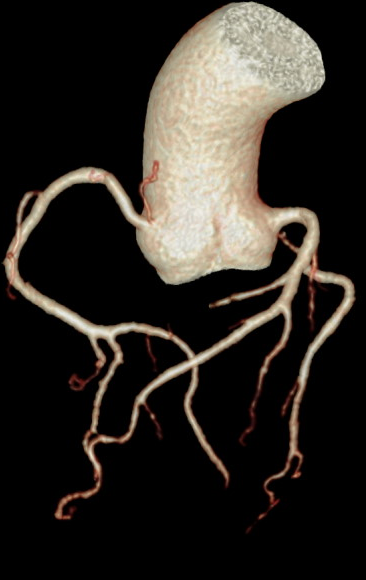

天河640层CT搭配前沿的AI人工智能技术,一键提取血管,观察病变立体直观。痛风石能谱成像、泌尿系结石成份分析助力临床治疗方案选择。

图片说明:肝脏病变3D成像、痛风石能谱成像